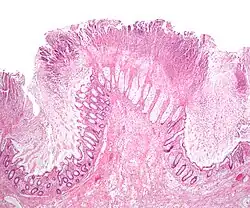

La colitis pseudomembranosa es una inflamación del colon (colitis) que se produce cuando, en determinadas circunstancias, la bacteria llamada Clostridium difficile lesiona el órgano mediante su toxina y produce diarrea y aparición en el interior del colon de unas placas blanquecinas llamadas pseudomembranas.[2] Casi siempre aparece en personas tratadas previamente con antibióticos, y en personas debilitadas ingresadas en hospitales o residencias de ancianos. La enfermedad se caracteriza por una diarrea, a veces de olor fétido, fiebre y dolor abdominal y puede llegar a ser grave y en algunos casos mortal (6-30%)

Lo más importante es la prevención: que el personal que atiende a personas encamadas o débiles, se lave bien las manos (basta con un jabón normal). Si aparece, se diagnostica mediante la determinación en heces de la toxina del C. difficile. Si hay duda, una colonoscopia puede mostrar las placas típicas de la enfermedad, El tratamiento consiste en la administración de un antibiótico contra C. difficile, generalmente metronidazol o vancomicina, en cualquier caso por vía oral. Últimamente también está disponible la rifaximina.